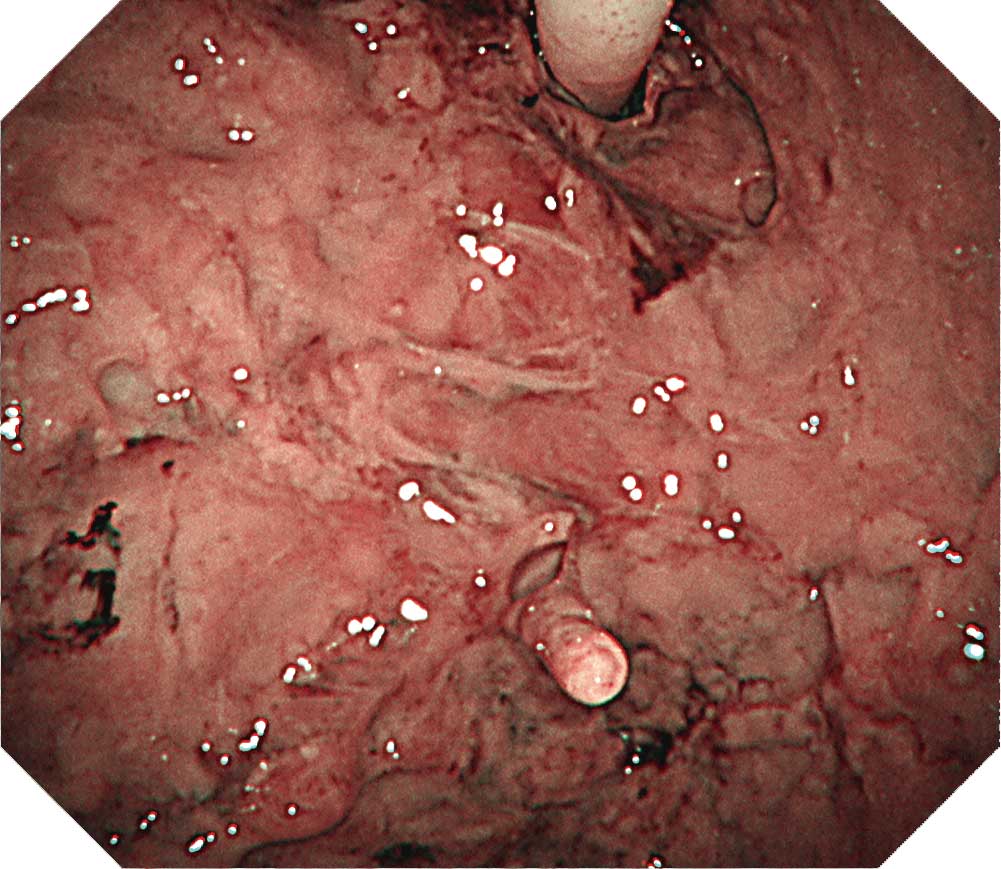

【症例G-2】左後壁

厚く斑状に隆起した胸膜と稠密性に集簇した結節を認める